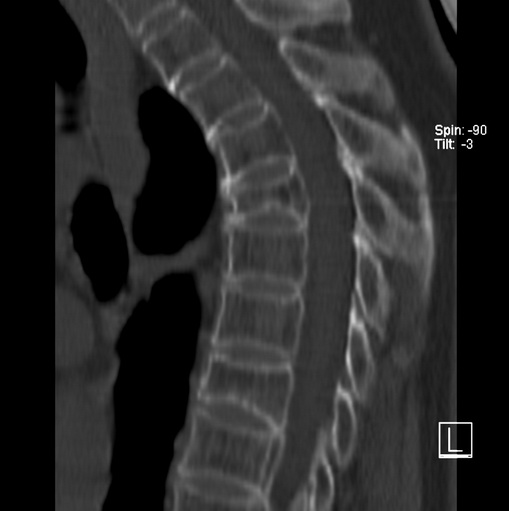

女、73、胸痛、胸闷3个月,无明显外伤病史,x线疑t4、t7陈旧压缩骨折,ct未经明显骨折,请问结论如何报?

老年女性病人,骨质稀疏,有些驼背,t4明显变扁,t7略变扁,椎体边缘无中断,骨小梁排列正常,无嵌插所致致密线。结合无明显外伤史,考虑老年骨质稀疏,慢性压缩改变,正如老年人骨质稀疏椎体呈双凹改变一样。我考虑报:老年骨质稀疏,t4、t7楔形变,脊柱曲度改变(驼背).敬请大家指教。

1)多个胸椎陈旧性压缩性骨折。2)胸椎普遍性骨质疏松。3)胸椎退行性改变。